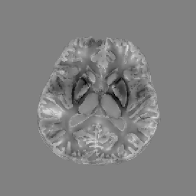

Figs. 14 and 15 display the visual comparisons of the direct approaches and the wavelet frame regularization approaches, and the zoom-in views of Fig. 14 are provided in Fig. 16. We also provide the visual comparisons of the direct approaches and the TGV regularization approaches in Figs. 17, 18 and 19. Since the reference image is not available for in vivo MR data, it is in general more difficult to provide quantitative evaluations than the numerical brain phantom. Nonetheless, we can see from the viewpoint of visual comparison that the pros and cons are almost the same as the numerical brain phantom experiments. It is also worth noting that the HIRE models can reduce the streaking artifacts which propagate from ΩΩ\partial\Omega into ΩΩ\Omega as well as the shadow artifacts. As pointed out in [52], the in vivo local field data is prone to the outliers near ΩΩ\partial\Omega because the GRE signal lacks information outside ΩΩ\Omega. Hence, we can see that most streaking artifacts propagate from these outliers near ΩΩ\partial\Omega into the ROI. However, thanks to the sparsity promoting property of 1subscript1\ell_{1} norm, the term λv1𝜆subscriptnorm𝑣1\lambda\left\|{\mathscr{L}}v\right\|_{1} in the HIRE approaches can somehow capture and remove them, leading to the suppression of artifacts propagating from ΩΩ\partial\Omega into ΩΩ\Omega as well as the shadow and streaking artifact removal. Finally, even though we can also note that the Tikhonov regularization can somehow reduce the artifacts, there are some losses of features due to the smoothness prior of the susceptibility image.

Figure 14: Sagittal slice images comparing QSM reconstruction methods for the in vivo MR data experiments with the wavelet frame regularization. All images of in vivo MR data experimental results are displayed in the window level [0.2,0.2]0.20.2[-0.2,0.2] for the fair comparison.

Figure 15: Axial slice images comparing QSM reconstruction methods for the in vivo MR data experiments with the wavelet frame Regularization.